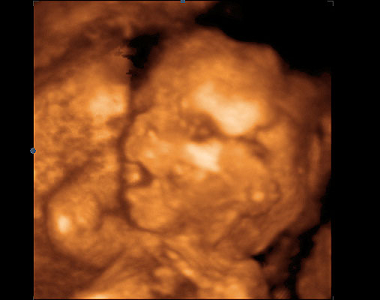

Snímky z ultrazvuku:

Sonogram 1: Trojrozměrné zobrazení plodu ve 14. týdnu vývoje (16. týden těhotenství). Plod je zachycen z profilu, shora dolů jsou šipkami označeny: čelo, nos, brada, žebra, stehenní kost.

Sonogram 2: Snímek plodu ve 14. týdnu vývoje (16. týden těhotenství). Plod si zakrývá levou rukou obličej, shora dolů jsou šipkami označeny: levá ruka s prstíky, paže, páteř.

Sonogram 3: Snímek plodu ve 14. týdnu vývoje (16. týden těhotenství). Snímek zachycuje dolní končetiny plodu a bederní páteř, shora dolů jsou šipkami označeny: stehno, lýtko, chodidlo.